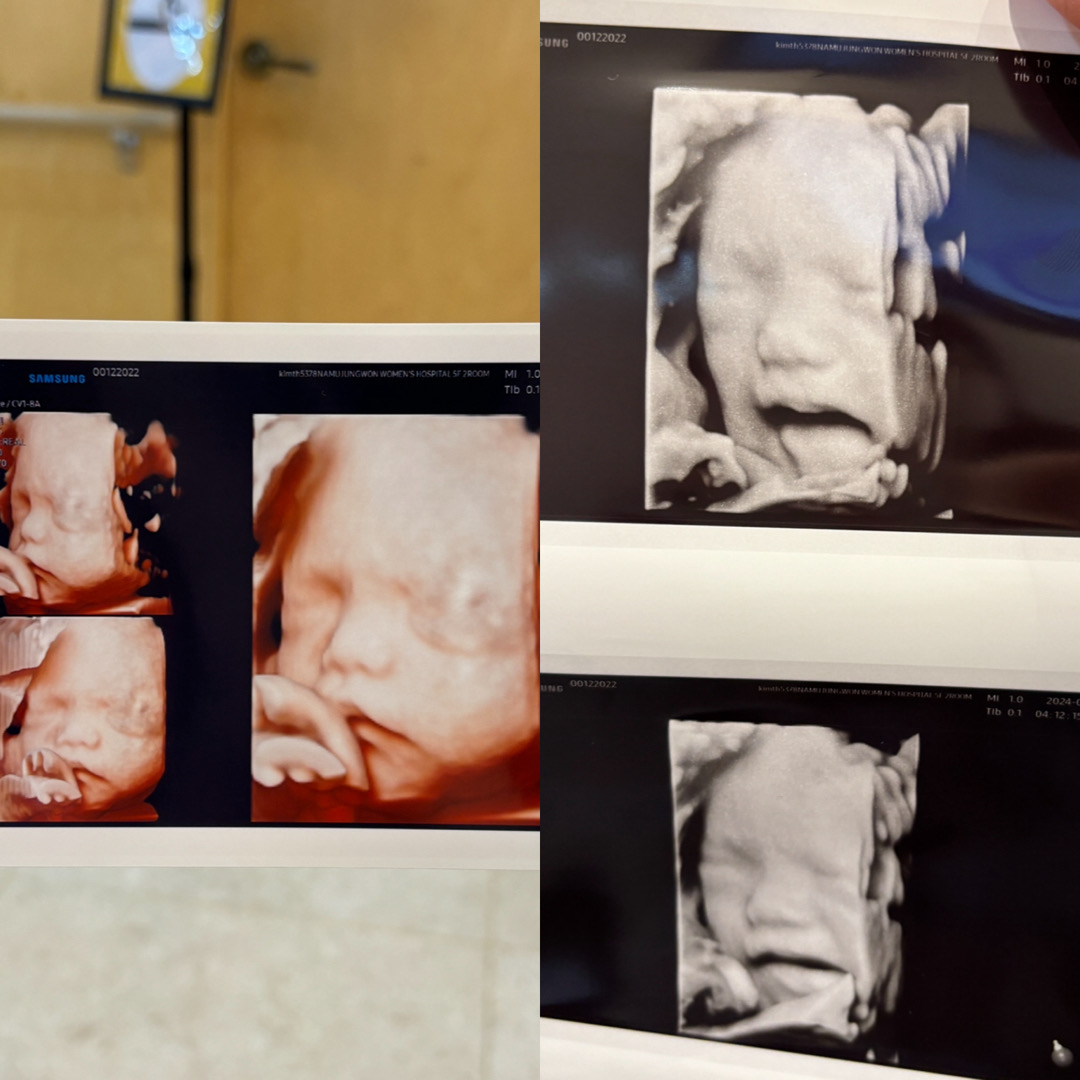

입초 성공 표정이 다양하네요 ㅋㅋㅋ

정밀초음파는 등돌리고 있었어서 한시간반넘게 했는데 입체초음파는 20분도 안걸렸어요☺️ 손으로 얼굴을 가려서 선생님이 계속 흔들었더니 뿌앵하네욬ㅋㅋㅋㅋㅋㅋㅋㅋ 베이비페이스 할까 고민인데 다들 하셨나요?

전 처음에 아가가 폴더로 접어서 얼굴앞에 발바닥이 보였는뎈ㅋㅋㅋㅋ 달래면서 배 흔드니까 살짝 내려줄때마다 순간포착해주셨어요!!! 또미엄마님두 입초 성공하실거예요😊